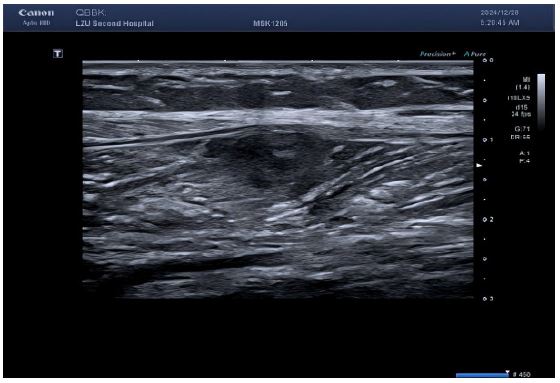

Imaging studies

Lower limb ultrasound: Detected a hypoechoic lesion within the intermuscular space of the right calf. Initial impression: Schwannoma suspected; CEUS recommended.

CEUS (performed next day): Subsequent CEUS performed 24 hours post-initial scan demonstrated heterogeneous enhancement at 25 seconds post-contrast injection, characterized by peripheral hyper-enhancement and a large central non-enhancing area – an imaging pattern misinterpreted as indicative of a benign lesion.

The reasons for the misdiagnosis of this patient as a benign tumor were as follows: (1) The initial diagnostic context involved routine ultrasound without documented extramuscular malignancy, precluding sufficient justification for metastatic suspicion; (2) Sonomorphological mimicry manifested as well-circumscribed, spindle-shaped anechoic foci with smooth margins, distinct hyperechoic capsules, and posterior acoustic enhancement within the calf musculature—features pathognomonic for schwannoma yet discordant with the infiltrative borders characteristic of aggressive malignancies; (3) Vascular analysis (Figure B) revealed sparse punctate vascular signals rather than the abundant internal/peripheral flow or large perforating vessels typical of subcutaneous cancers; (4) CEUS kinetics further reinforced misdiagnosis through arterial-phase peripheral hyper-enhancement with central non-enhancing zones, maintained circumscribed margins, and early washout in adjacent tissues—collectively aligning with classical benign enhancement profiles and creating a compelling illusion of non-malignant pathology.